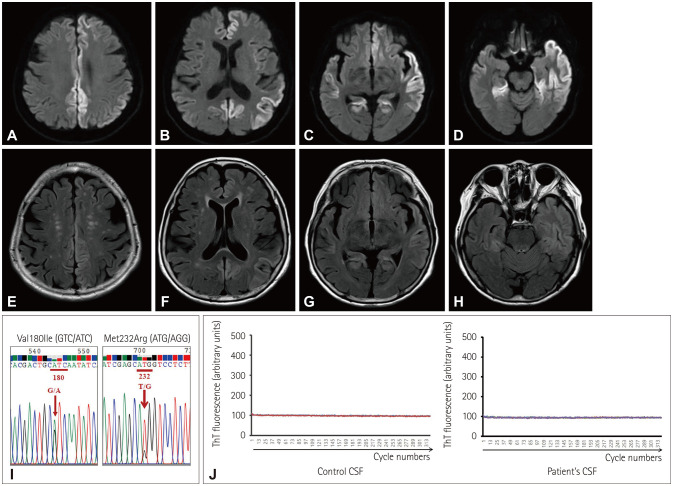

Creutzfeldt-Jakob Disease With Double Mutations at Codon 180 and Codon 232 of PRNP.

克雅氏病伴PRNP密码子180和232双突变。